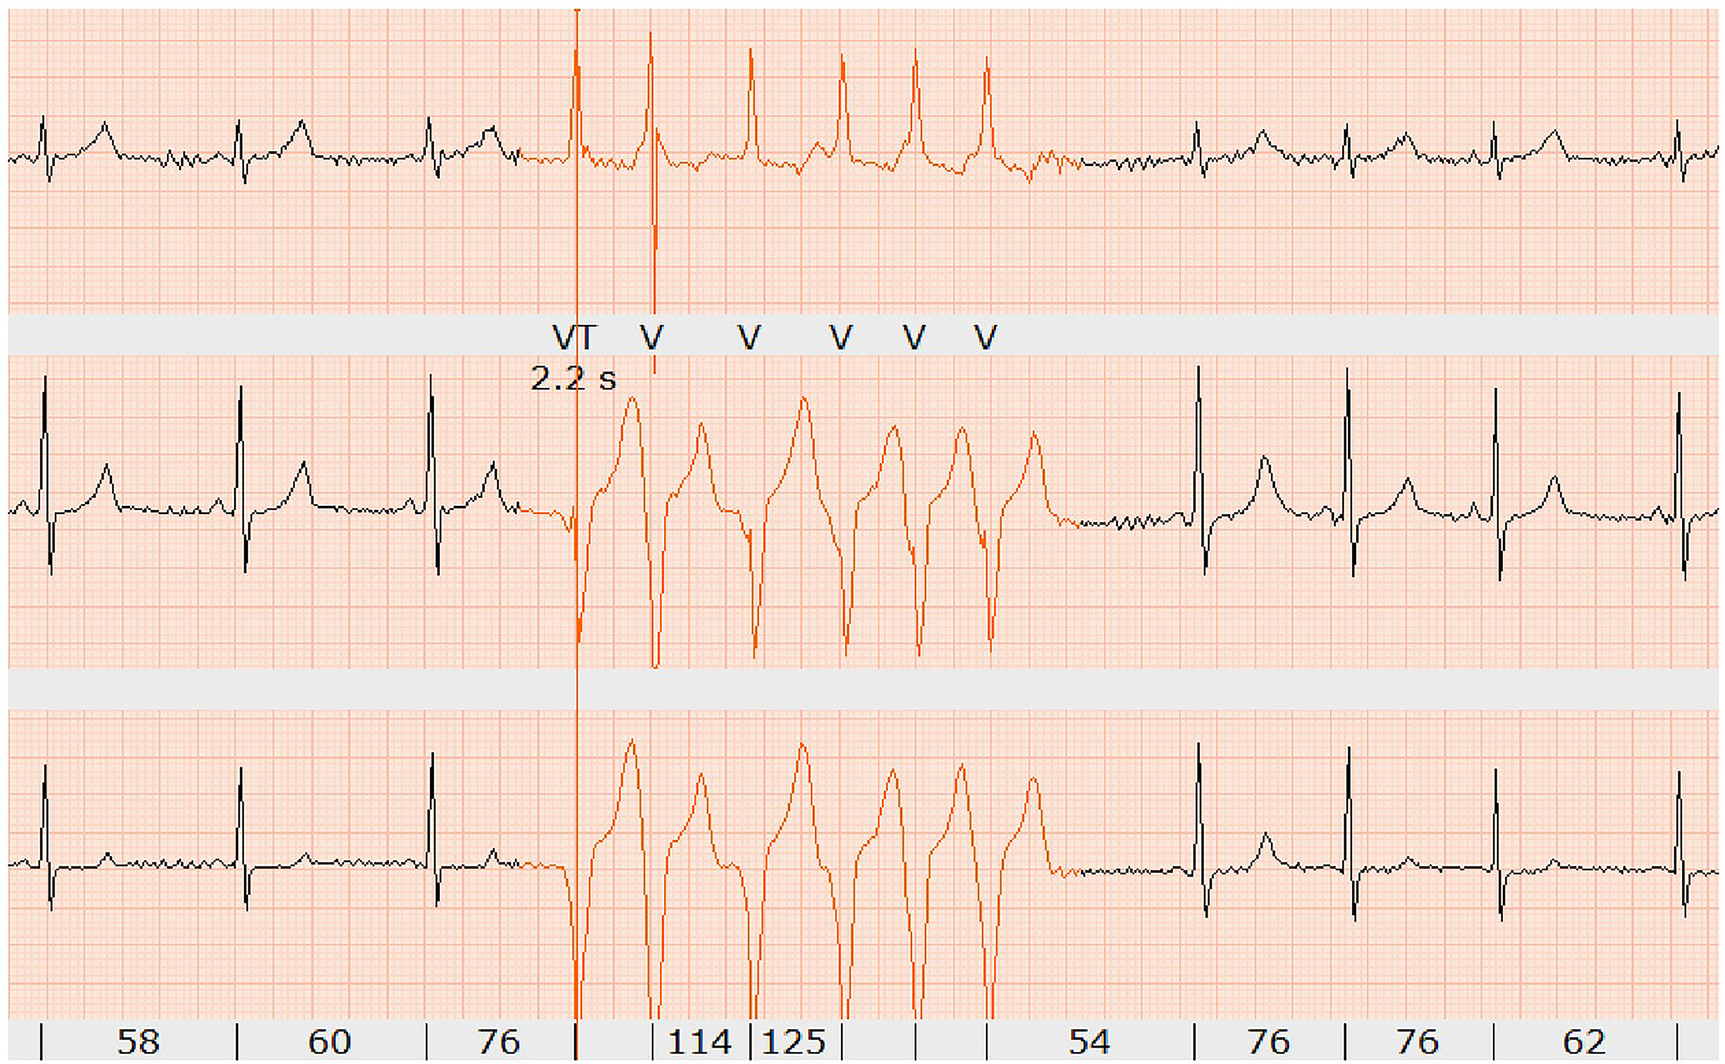

During the placement of the venous cannula for the injection of the CMR contrast agent, the athlete fainted and showed asystole for 18 s, which was captured by Holter monitoring. No previous syncope or palpitations had been reported. During the regular follow-up period, Holter monitoring was added, which displayed short, non-sustained ventricular tachycardia during rest (Figure 4). As this was three-lead Holter monitoring, the origin of the tachycardia could not be located.

Figure 4. Holter monitoring showing short non-sustained ventricular tachycardia (six beats in red) at rest (confirmed by two independent electrophysiologists).